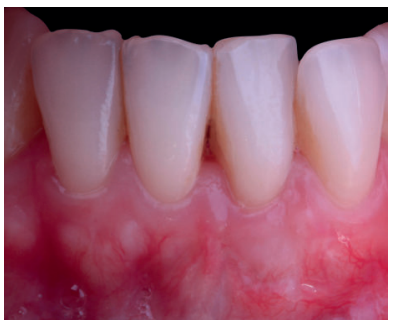

El control a la semana (Figura 13) presentaba inflamación moderada y a las 2 semanas (Figura 14) se retiraron los puntos de sutura. La paciente acudió a los 4 meses (Figura 15) y al año (Figura 16) a visitas de revisión, donde se apreció una buena banda de tejido queratinizado y una pequeña cicatriz.

Los presentes casos clínicos demuestran que la técnica de Edlan-Mejchar modificada (vestibuloplastia + ITC) es eficaz para el tratamiento de recesiones gingivales unitarias y múltiples con 1 mm o menos de tejido queratinizado apical en el sector anteroinferior, presentando estabilidad después de 18 meses.

Una limitación de la técnica quirúrgica es la formación de una pequeña cicatriz en el fondo del vestíbulo. Bethaz y cols.19 encuentran, tras la maduración de los tejidos, la formación de una pequeña cicatriz en 5 de los 7 casos (71.4%). Se puede observar la formación de una pequeña cicatriz en el segundo caso clínico presentado, no existiendo formación de dicha cicatriz en el primer caso clínico.